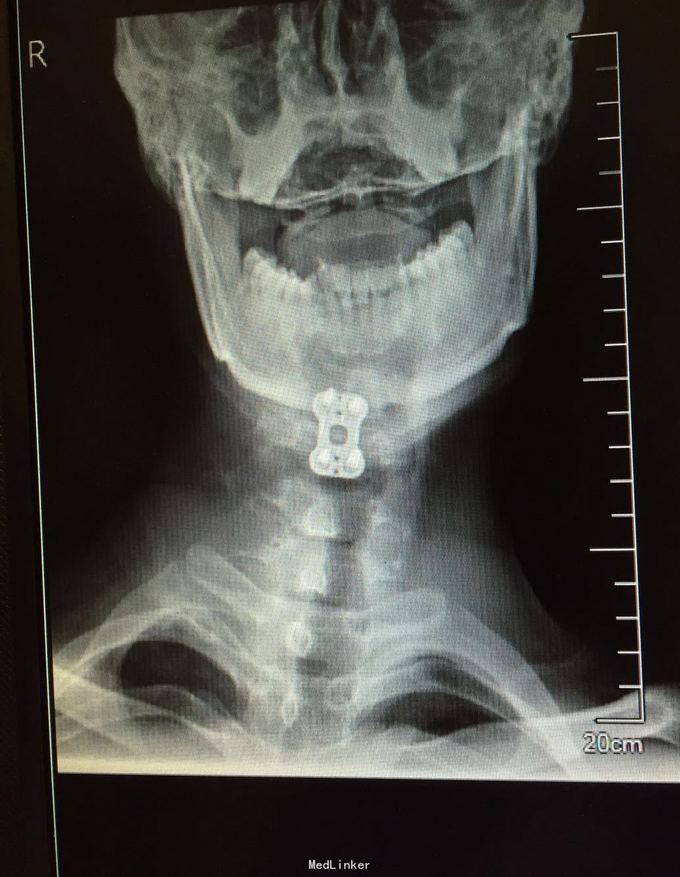

患者,男,36岁,2月前因外伤致颈部疼痛,右前臂麻木活动受限,持物时无力。

专科检查:颈椎生理弯曲变直颈椎各棘突及椎旁压痛,向右前臂放射,颈椎活动度,前屈60度,后伸20度,左屈40度,右屈40度,左侧旋转45度,右侧旋转45度,右上肢前臂感觉减低,运动差,双侧HOFFMAN症阳性。辅助检查:颈椎正侧位颈部4椎体向前滑脱。

初步诊断:颈部4椎体滑脱伴颈髓损伤